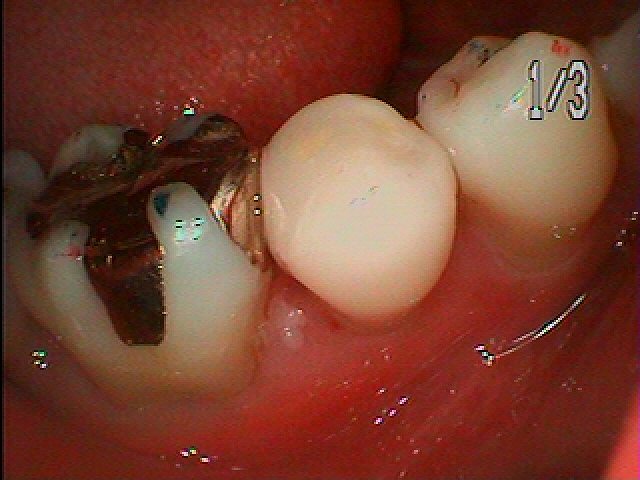

銀歯をすべてセラミックへやり変えていきます セラミックを用いた臨床例 審美治療|お知らせ |広島市安佐南区の歯科医院 銀歯をすべてセラミックへやり変えていきます セラミックを用いた臨床例 審美治療 トップ お知らせ・ブログ お知らせ 銀歯をすべてセラミックへやり変えていきます セラミックを用いた臨床例 審美治療 銀歯をすべてセラミックへやり変えていきます セラミックを用いた臨床例 審美治療 左上の6番部になります この銀歯を外して虫歯治療を行っていきます 中はこのようになっていました 近心部の虫歯を除去していきました CR樹脂にて覆罩を行っています セレックセラミックにて修復しています 銀歯が外れたとのこと わずかに虫歯が存在していました セレックセラミックにて修復しています 綺麗に仕上がりました Web診療予約 初めての方へ 選ばれ続ける理由 院内設備について 歯が痛いしみる一般歯科 歯がぐらぐらする歯周病 健康な歯を保ちたい予防歯科 子供の虫歯予防をしたい小児歯科 銀歯をセラミックに審美歯科 白い歯を目指しませんか?ホワイトニング 矯正専門医がいるので安心矯正歯科 抜けた歯を補いたいインプラント・入れ歯 医院案内 スタッフ紹介 メリィハウス歯科クリニックオフィシャルホームページ ラベンダー歯科クリニックオフィシャルホームページ お知らせ・ブログ ホーム 診療科目 一般歯科 歯周病治療 予防治療 小児歯科 審美治療 ホワイトニング 矯正歯科 入れ歯・インプラント マウスピース矯正 初めての方へ 院長・スタッフ 設備紹介 医院案内・アクセス メニューを閉じる